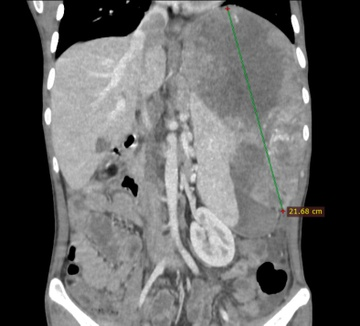

Ung thư gan: Sát thủ thầm lặng với tỷ lệ tử vong cao

VOVVN - VOV.VN - Ung thư gan là căn bệnh tiến triển âm thầm, đa số phát hiện muộn, khiến việc điều trị gặp nhiều khó khăn. Câu chuyện của chàng trai 25 tuổi thoát chết sau...